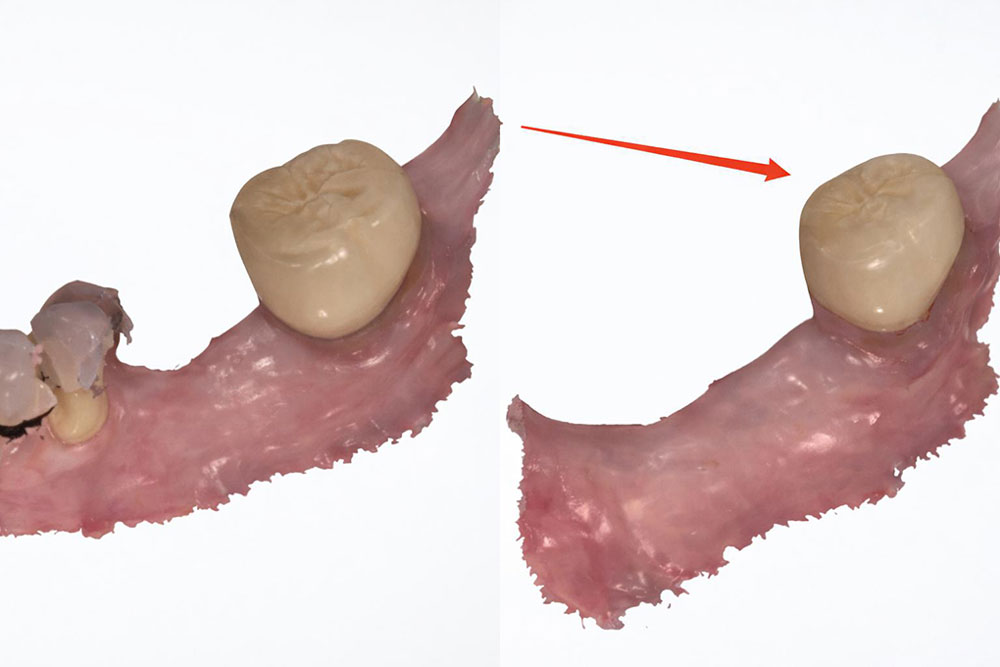

2. Correct way for Fit to partial

Now let’s look at another example. In the first scan (the left picture), the dentist took off the partial, and scanned the natural tooth. In the second scan, the dentist prepared the natural tooth, and scanned the prepared tooth. That was the correct way for Fit to partial cases.

Right way for fit to partial dental cases